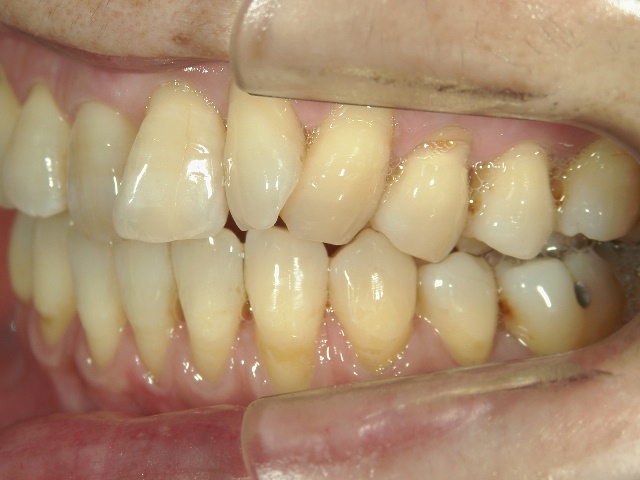

矯正歯科 治療前矯正歯科 治療前

矯正歯科 治療前

no.12_5333_治療前_左.jpgno.12_5333_治療前_正面.jpgno.12_5333_治療前_右.jpg